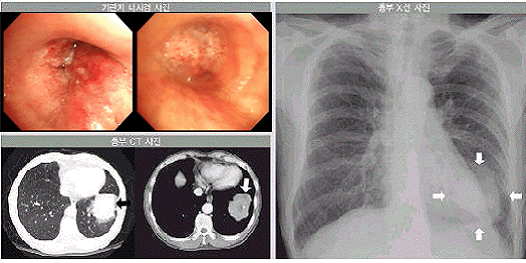

폐암

폐암이란 폐에 생긴 악성 종양을 말하며, 암세포가 폐를 구성하는 조직에서 발생한 원발성 폐암과 암세포가 다른 기관에서 생겨나 혈관이나 림프관을 타고 폐로 이동해 증식하는 전이성 폐암으로 나눌 수 있다.